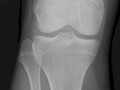

An extremity X-ray is a picture of your hand, wrist, arm, foot, ankle, knee, hip, or leg. It is done to see whether a bone has been fractured or a joint dislocated. It is also used to check for an injury or damage from conditions such as an infection, arthritis, bone growths (tumours), or other bone diseases, such as osteoporosis.

Extremity X-rays are done to:

• Find the cause of pain in an extremity.

• See if your bone is fractured or your joint is dislocated.

• See if fluid has built up in the joint or around a bone.

• See if your bones are positioned properly after treatment for a fracture or dislocation, such as after placing a cast or splint on an arm or leg. An X-ray also may be done after a doctor places a device such as a pin or an artificial joint in a bone.

• Find changes in your bones caused by conditions such as an infection, arthritis, bone growths (tumours), osteoarthritis of the hip, osteoarthritis of the knee, or other bone diseases.

• Find foreign objects such as pieces of glass or metal.

• Check to see if a child's bones are growing normally.

• See if your bones and joints are in the correct position after joint replacement surgery.